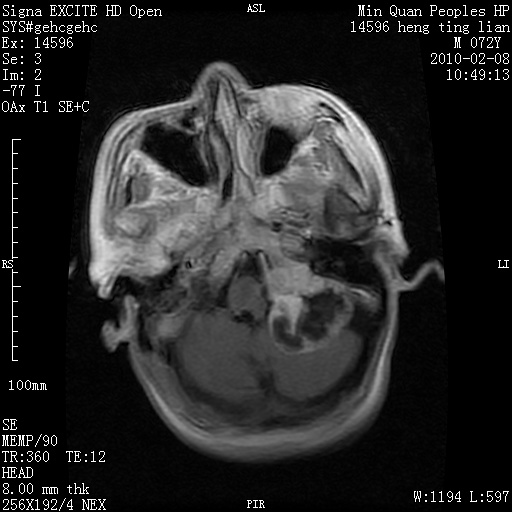

m,72,头疼,头晕两年,伴视力模糊三月,饮食呛咳两天。pe:颈部抵抗,左眼突出,左眼瞳孔约3mm,对光反射消失,双眼失明,伸舌困难,双肺呼吸音粗,心率110次/分,左上肢肌力i级,左下肢屈曲,肌张力高。现有08年2月19mri平扫及10年2月8日mri增强请会诊。ct病灶呈低密度伴散在点、片状等密度区,无明确钙化(无ct片资料可供上传)。[

脑外肿瘤,囊实性,环状不规则强化,内听道扩大,考虑神经源性肿瘤

左侧桥小脑区占位伴梗阻性脑积水----考虑 1神经鞘瘤 2室管膜瘤。

左侧桥小脑区神经鞘瘤伴梗阻性脑积水。

听神经瘤

脑外肿瘤,病灶呈匍匐蔓延,表皮样囊肿可能性大。

脑外肿瘤,病灶呈匍匐蔓延,表皮样囊肿可能性大。支持!

左侧桥脑小脑角区肿瘤并脑积水,考虑听神经瘤,脑膜瘤?

考虑听神经瘤

左侧桥脑小脑角区肿瘤并脑积水,考虑听神经瘤,